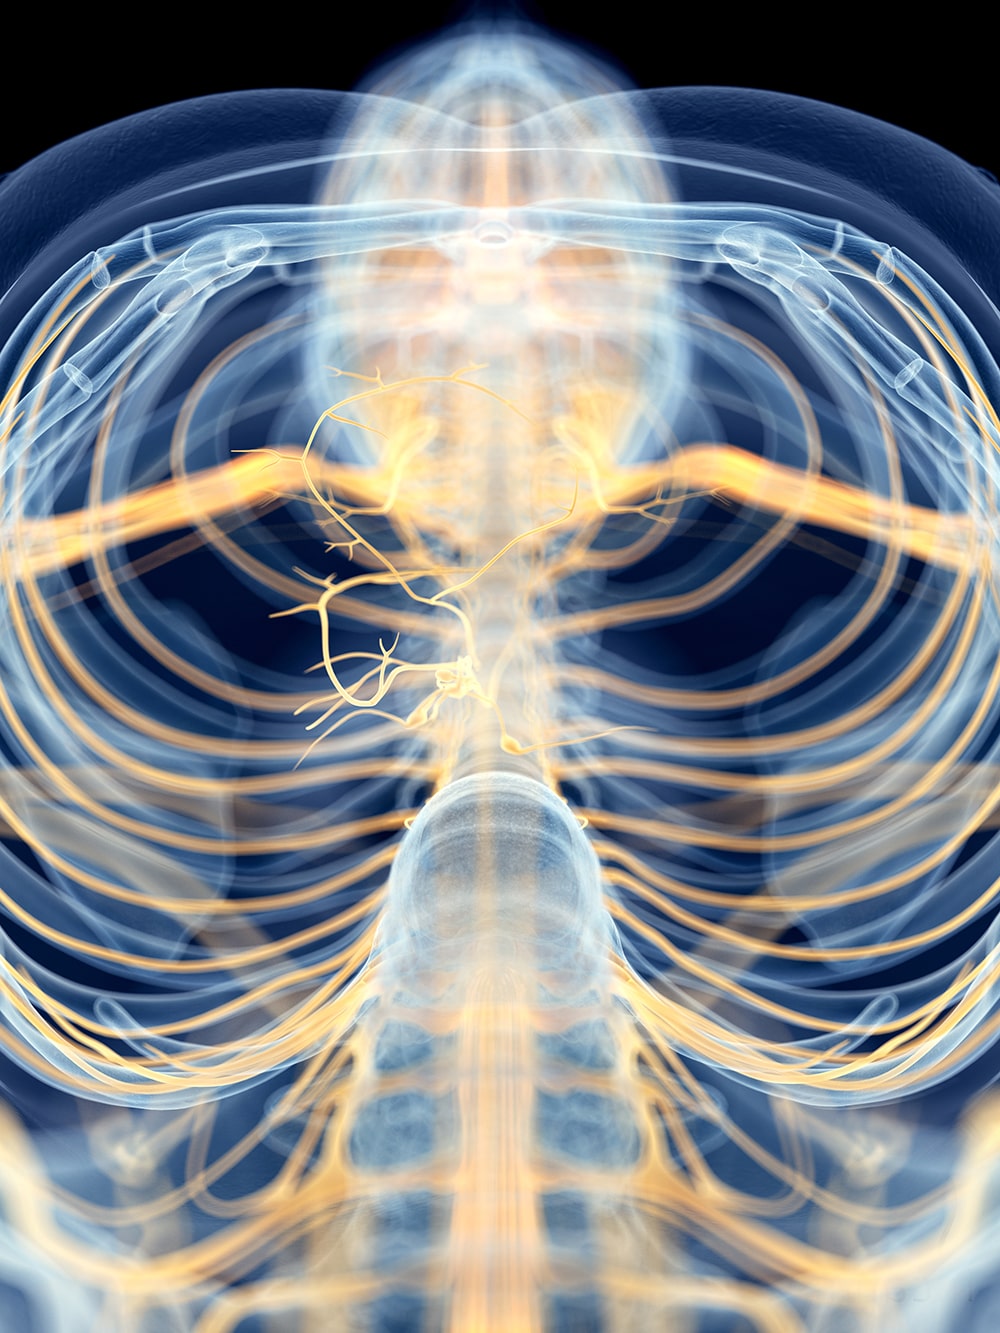

- The neural breakdown that leaves trauma survivors so vulnerable to future trauma

- The specific way trauma impacts the hierarchy of the nervous system’s response

- How trauma retunes the nervous system to be oversensitive to threats

- How to activate the part of the nervous system that promotes stronger social engagement

- How to shift a client’s physiological state to move them out of shutdown